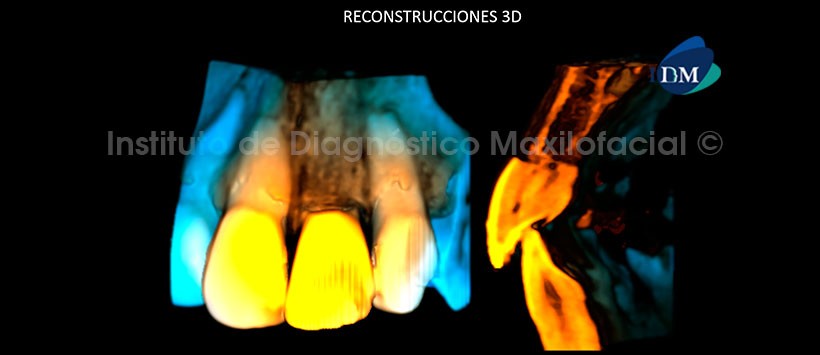

En las reconstrucciones 3D se observa claramente la reabsorción externa severa con la pérdida total de soporte óseo. (Figura 5)

Conclusión: Reabsorción radicular externa severa de la pieza 2.1.